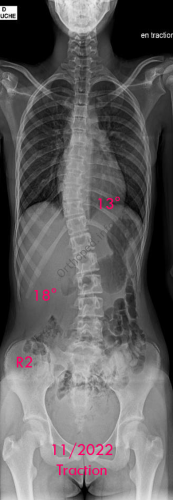

Images de scolioses opérées 16 janvier 202418 janvier 2023 par Damien Scoliose idiopathique - VBT -1 Chirurgie de modulation de croissance (VBT) Scoliose idiopathique - VBT -1 - pré-op Scoliose idiopathique - VBT -1 - pré-op en traction Cliché réalisé pour tester la réductibilité de la scoliose Scoliose idiopathique - VBT -1 - post-op immédiat Scoliose idiopathique - VBT -1 - 3 mois post-op Scoliose idiopathique - VBT -1 - 10 mois post-op